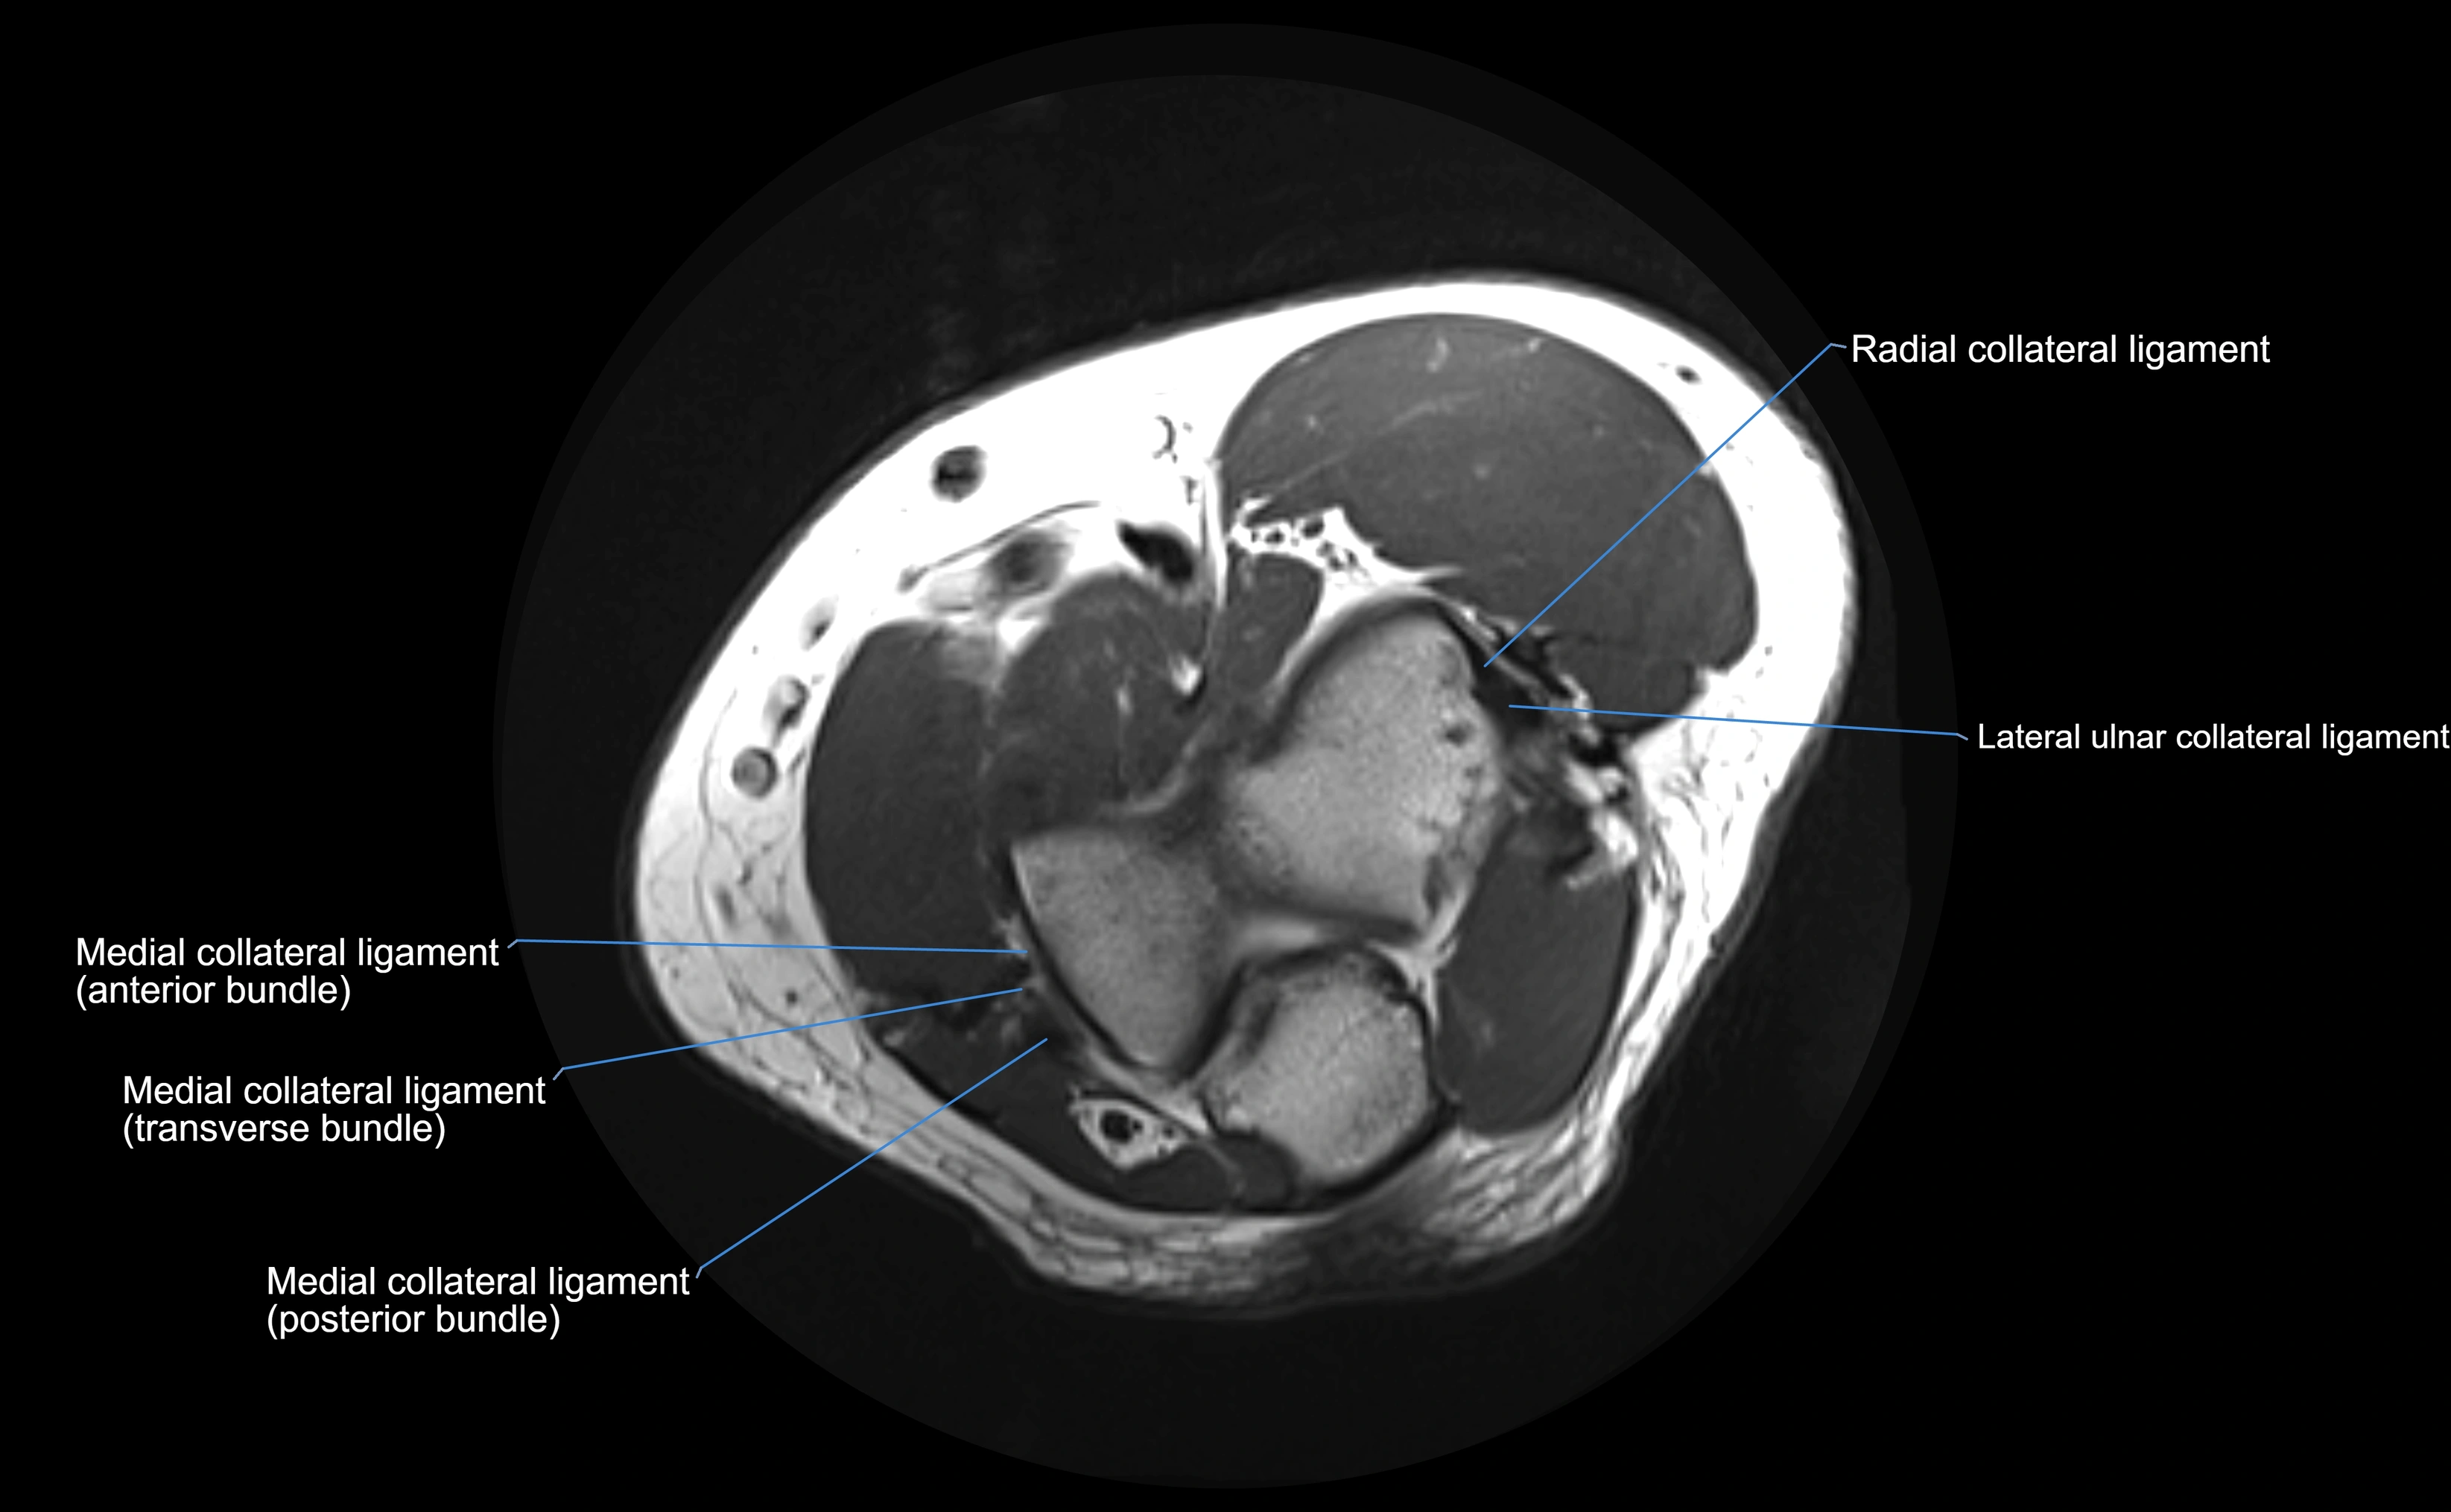

MRI Appearance

T1-weighted images:

• Ligament: low signal intensity (dark), appearing as a continuous band around the radial head.

• Adjacent fat and marrow: bright, creating contrast with the ligament.

• Thickening or disruption indicates injury or fibrosis.

• Joint capsule and synovium seen as thin low-signal lines contiguous with ligament margins.

T2-weighted images:

• Ligament: low signal (dark) with clear delineation from joint fluid.

• Fluid or edema: bright hyperintense, separating or surrounding the ligament in partial tears.

• Complete tear: discontinuity or non-visualization of ligament fibers, often with joint effusion.

Proton Density Fat-Saturated (PD FS):

• Normal: dark, well-defined band outlining the radial head.

• Partial tear: irregular or bright hyperintense signal within or adjacent to ligament fibers.

• Joint effusion and reactive synovitis appear bright and are well visualized.

MRI Arthrogram Appearance

• Contrast outlines the proximal radioulnar joint and radial head recess.

• Normal ligament appears as a dark ring surrounding the radial head, containing the injected contrast within the joint cavity.

• Partial tear: contrast extends along the ligament or beneath its fibers.

• Complete tear or subluxation: contrast extravasates around the radial head or ulna, indicating discontinuity.

• Detects capsular defects, instability, or synovial invagination with high sensitivity.